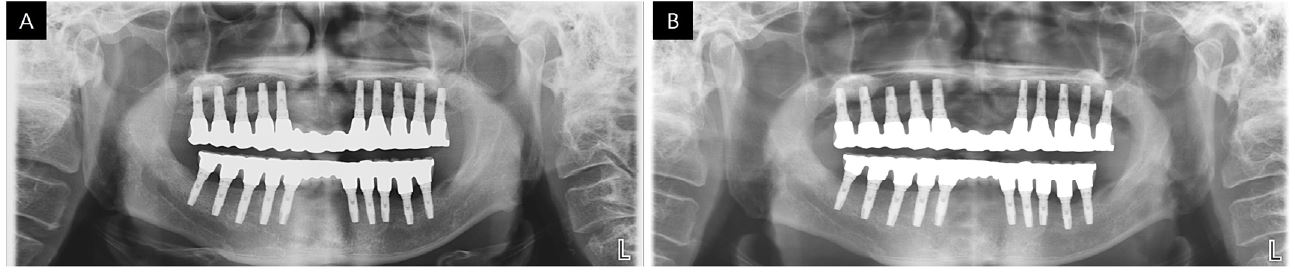

Finally, porcelain build up was performed with metal occlusion in the maxilla and porcelain occlusion in the mandible for esthetics. The abutments and final prosthesis were checked in the mouth and luted together with self-adhesive resin cement (RelyX U200; 3M ESPE) (Figs. 7 and 8). To remove excess resin cement and gain passive fit, the luted prostheses were removed from the mouth and connected to fixture analogs to make a cast, and hexagon surfaces were rounded off until no resistance was felt while tightening the screws. The provisional prostheses were reconnected, and the patient was instructed to visit after one week. Definitive prostheses were delivered to the patient after one week, and occlusal adjustments were made to obtain canine guidance upon eccentric movement and mutually protected occlusion upon anterior guidance. From the panoramic view, it can be seen that the prostheses were well connected to the fixtures (Fig. 9). To protect the porcelain occlusion from chipping, the patient was instructed to use a night guard every night.